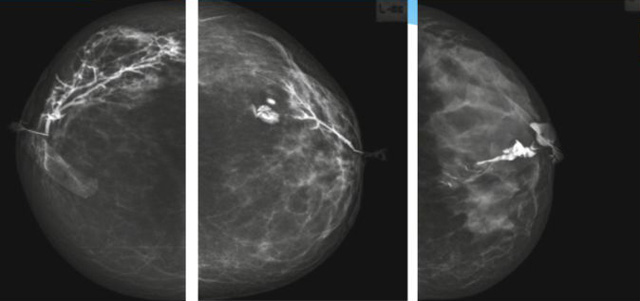

乳腺導管內乳頭狀瘤分為以下兩個,位于乳暈區大導管的中央型乳頭狀瘤,起源于末梢導管小葉單位的外周型乳頭狀瘤。外周型乳頭狀瘤常常沒有明顯的的臨床表現,常因X線或乳腺超聲設備檢查發現。重點要關注的是中央型乳頭狀瘤,發生于任何年齡的女性,以40~50歲者居多。它表現為:單側乳頭溢液,特別是血性溢液少數病人可在乳暈區觸及腫塊。從病理學上面講表現為導管上皮和間質增生形成有纖維脈管束的乳頭狀結構。這是它一個病理學上的表現。它的超聲表現為:病變導管囊狀擴張呈無回聲,內可見乳頭狀低回聲或中等回聲。乳暈處的導管擴張,管腔內可見邊界清楚的,低回聲實性結節。外周型導管內乳頭狀瘤可,表現擴張為為低回聲的實性結節,CDFI:部分腫瘤可顯示為軸心性的看到血流信號。乳腺增生癥:可見導管擴張,內無乳頭狀實性回聲,導管內乳頭狀癌:囊內乳頭狀癌病變較大,不規則,厚基底,血流豐富。以囊性為主的混合回聲,形態不規則,內見實性低回聲實性低回聲可見少量血流,病理為囊內乳頭狀癌。

乳腺超聲設備檢查的價值在哪里呢?它可以檢查發現乳暈周圍的各種病變,對于單側乳頭溢液、血性溢液的患者,超聲是首選的影像學檢查方法。注意:導管內乳頭狀瘤可合并不典型增生或,導管內乳頭狀癌,手術前懷疑時候,就應該手術切除而不是用微創手術。